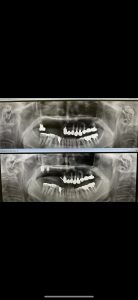

午後はI.O.Dインプラントオーバーデンチャーの確認

後方大臼歯に強固な固定源を設置する事により、沈下無し、顎関節も守り、こんなに小さい義歯フレームに変更出来る、噛み応えもグッド👍

落ち着いたら人工歯はメタルに置換

年明けは、左上ソケットリフト2本予定